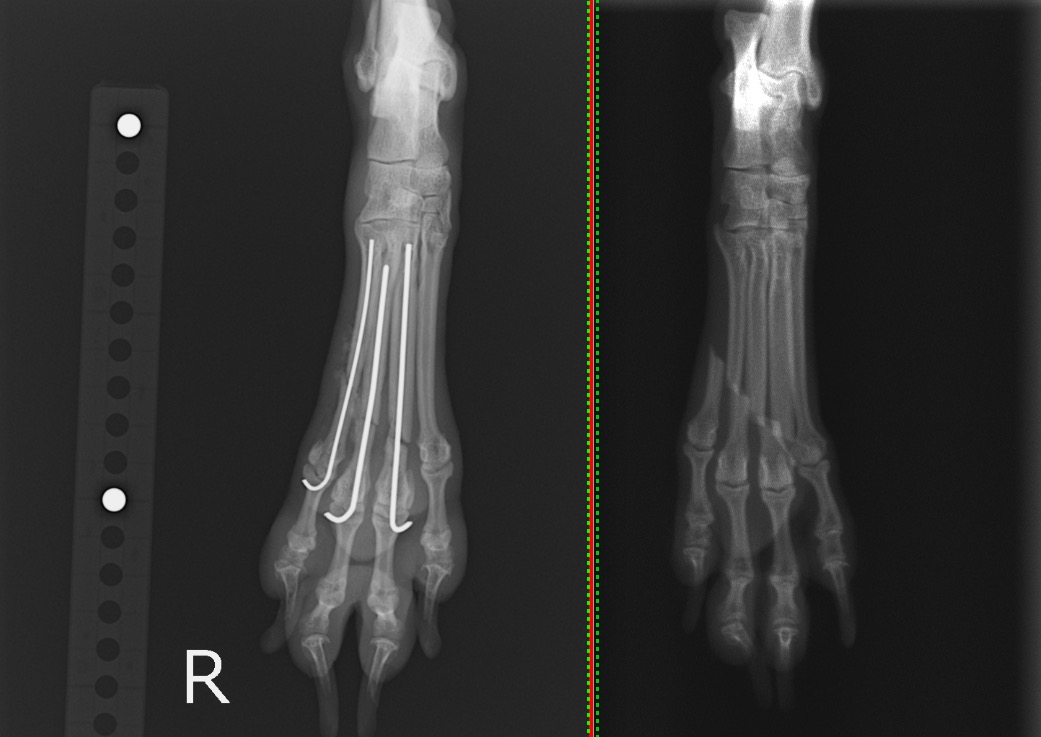

犬の中足骨骨折(0.6mmピン、0.8mmピン使用) 左:術後/右:術前